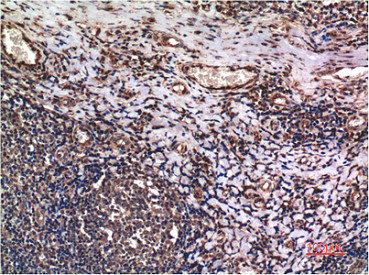

Immunohistochemical analysis of paraffin-embedded Human lung Tissue using Cyclin B1 Mouse mAb diluted at 1:200.